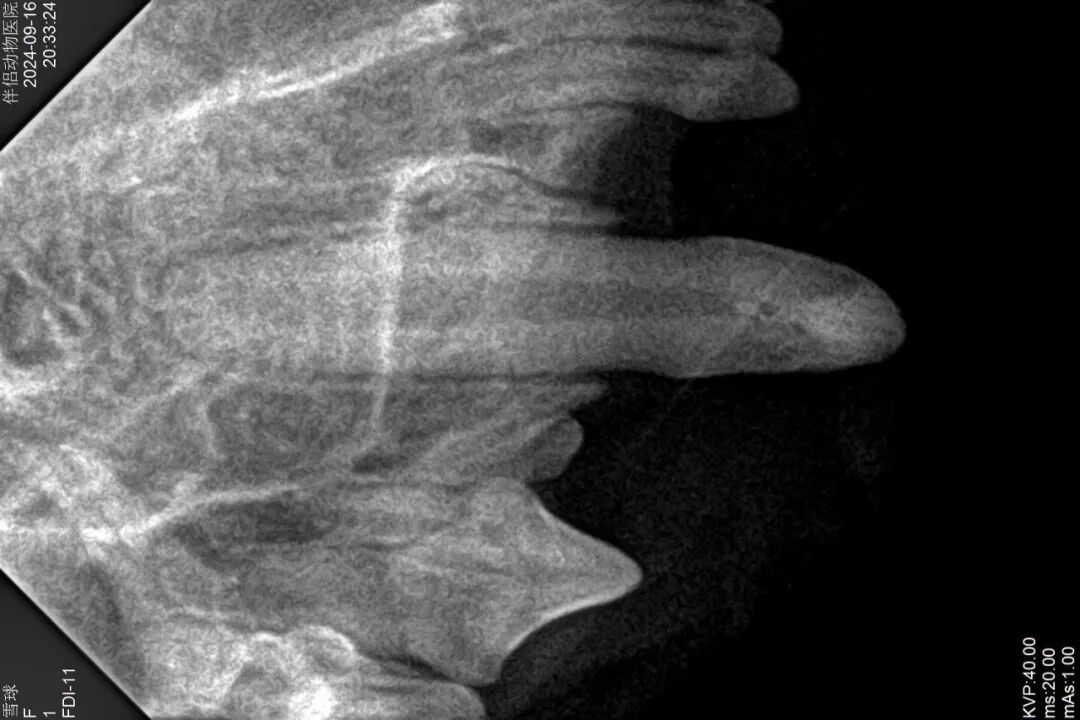

24、术后牙科DR

口腔光固化灯是什么光【病例分享】猫-牙科-活髓治疗_https://www.jmylbn.com_新闻资讯_第29张